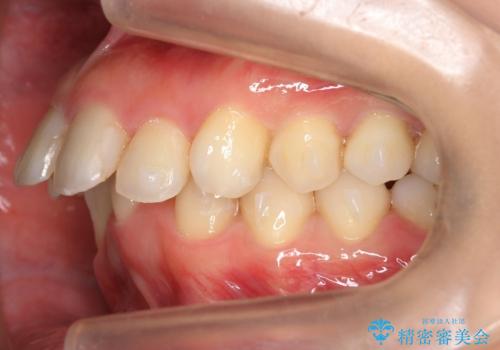

出っ歯 下の歯のガタガタ 下の前歯のみ1本抜歯 マウスピースで1年

- 出っ歯を主訴に来院。

古典的な方法では4本抜歯した後、ワイヤー矯正という方法も選択肢には上がりましたが、下の前歯を1本だけ抜くことにし、マウスピースで短期間で治療を終わらせるようにしました。

治療も比較的短期間で終わり、大変喜んでいただきました。

下の前歯を1本抜くと上下の正中はあいませんが、ほとんど目立ちません。